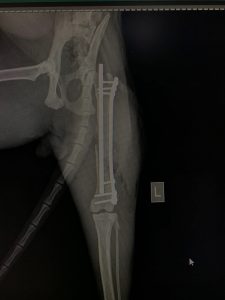

- Liječenje prijeloma kostiju, uključujući intraartikularne frakture

- Korektivne osteotomije za ispravljanje deformiteta